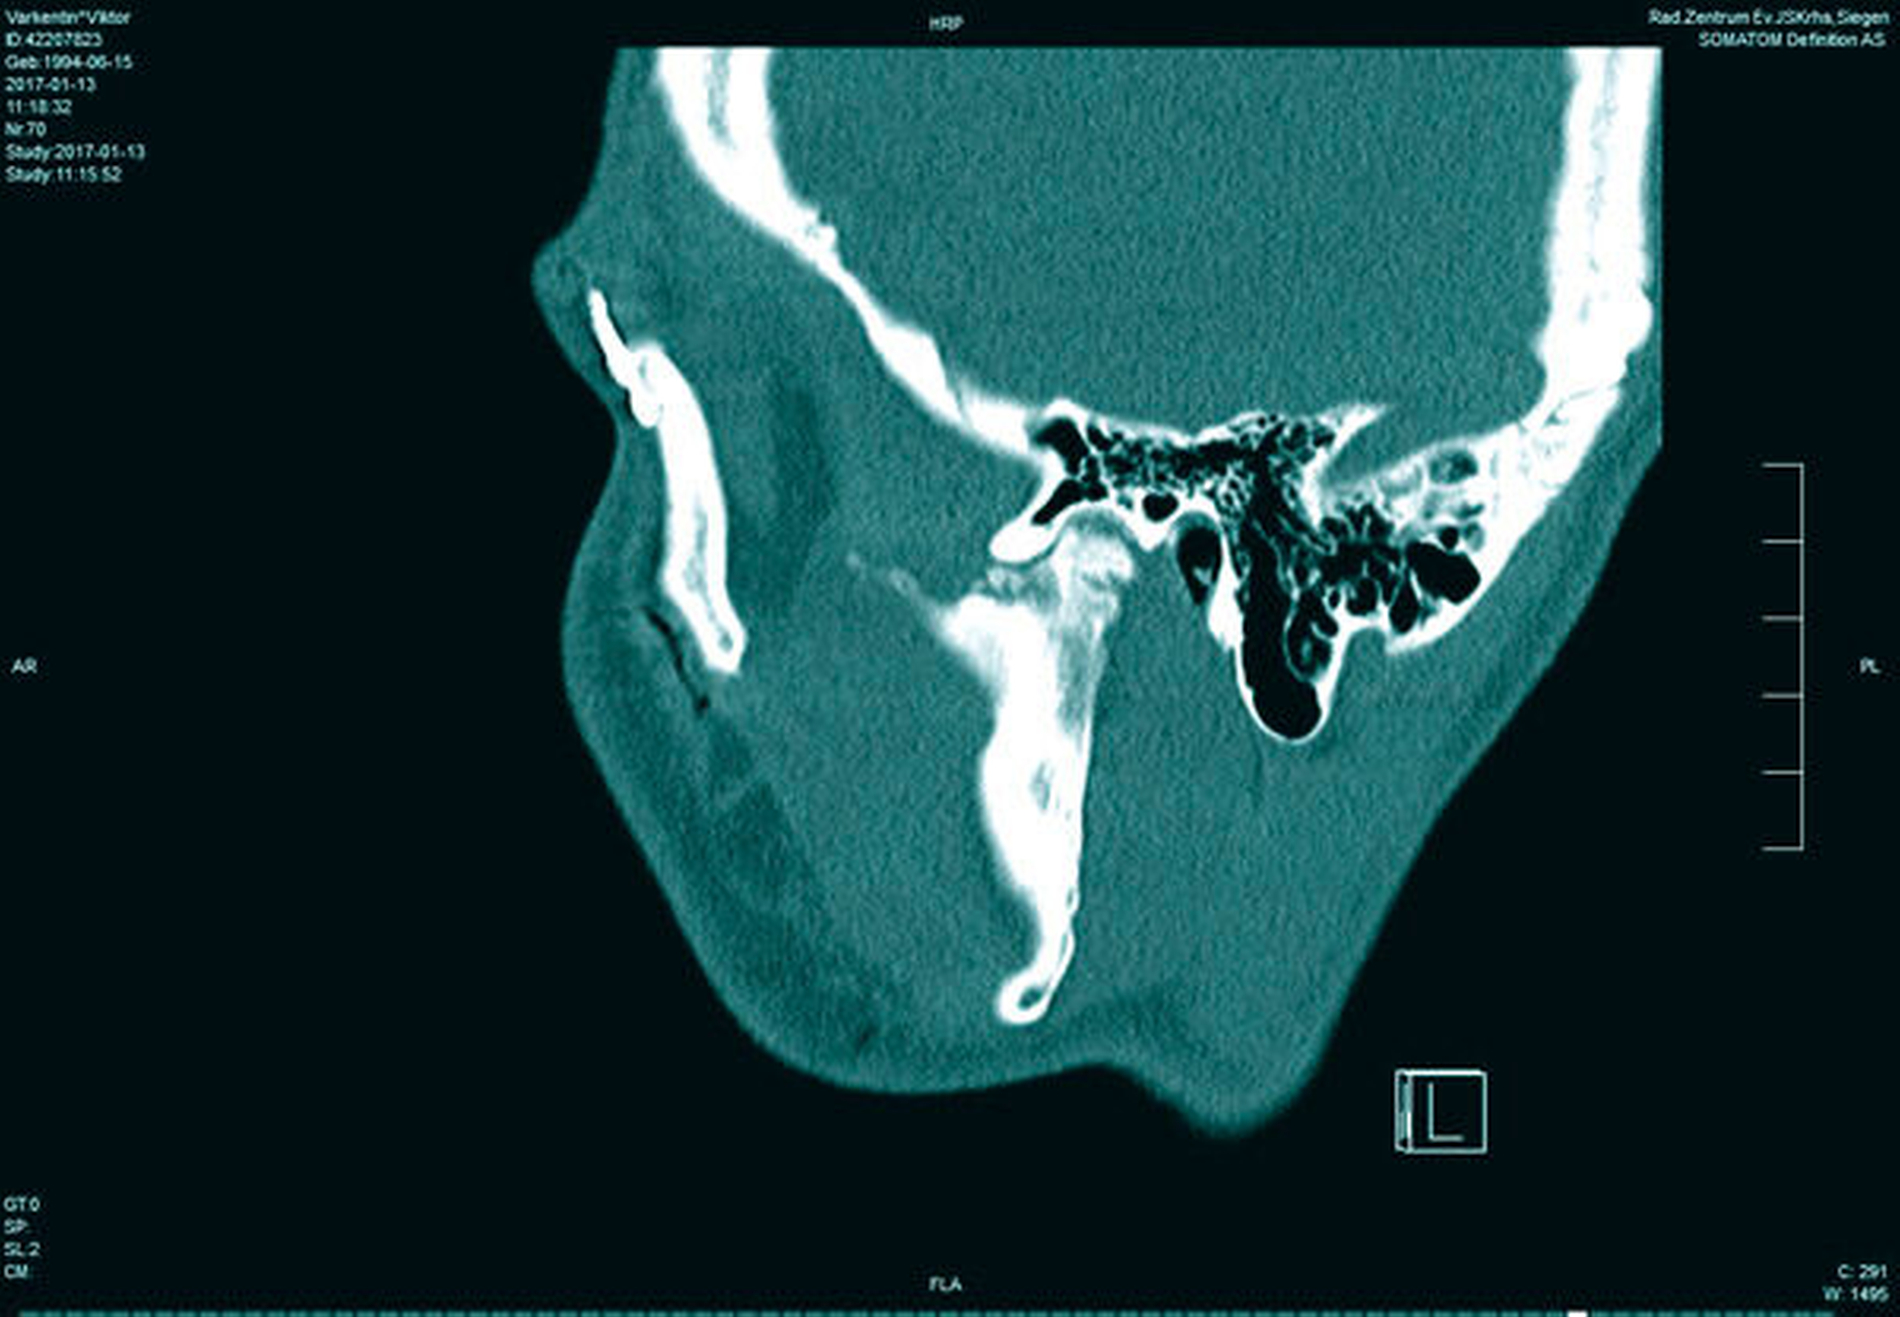

In der Folge entwickelte sich binnen fünf Monaten eine absolute Mundöffnungsbehinderung. Die SKD betrug null Millimeter. Passend zur klinischen Symptomatik zeigten sich radiologisch die Zeichen einer knöchernen Ankylose der Kiefergelenke beidseits Typ III nach Sawhney [1986] (Abbildung 1a bis 1d).